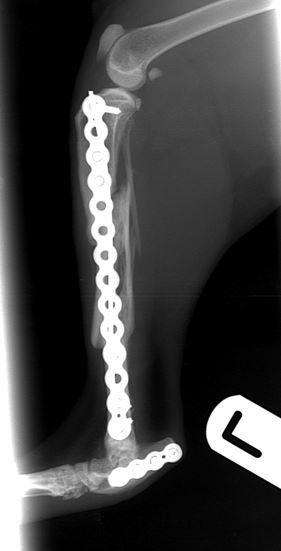

Fig. 2 Immediate post-operative radiographs. A 2.4mm PAX plate with an intra-medullary pin has been used to repair the tibial fracture. A 2.0mm PAX plate has been used to repair the comminuted calcaneal fracture